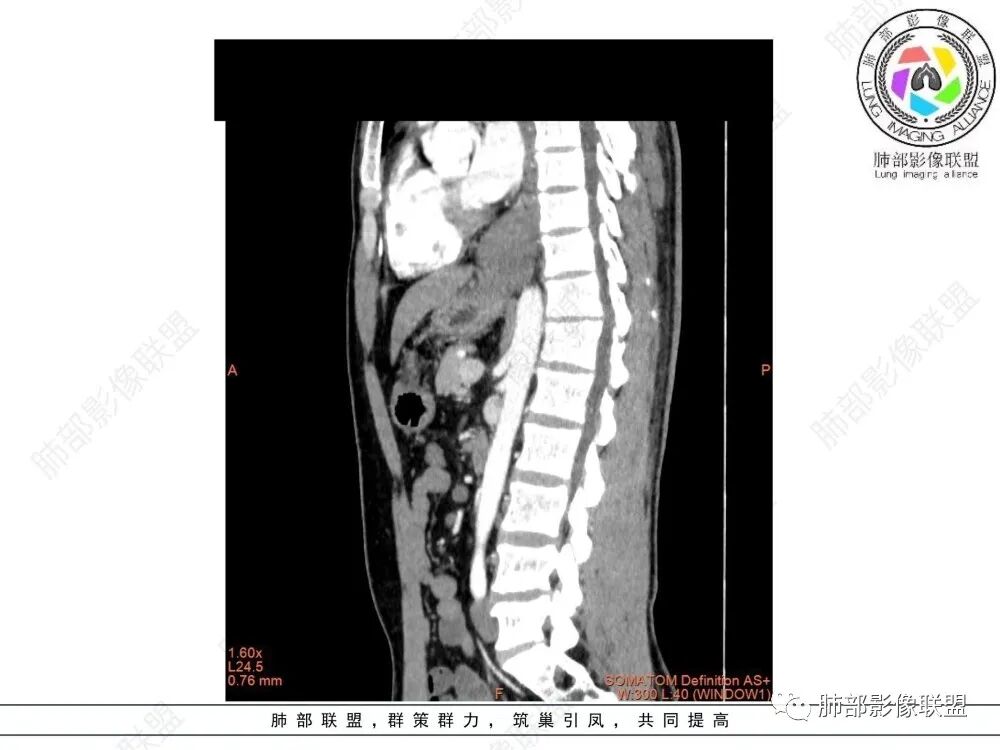

食管下段近贲门处肿块,食道受压变窄,粘膜无破坏,轻度强化,T2等低信号,考虑平滑肌瘤?神经鞘瘤?鉴别间质瘤。

定位后纵膈,实性密度,增强轻度强化,T1等低信号T2低信号,弥散未受限。钡餐造影,食道及贲门管壁柔和,造影剂通过顺畅。考虑神经鞘瘤。鉴别食道平滑肌瘤。

食管下段肿块,环壁生长,分叶状,密度比较均匀,钡餐造影食管下段弧形受压移位,并可见龛影,考虑为食管平滑肌瘤或食管结核。

后面造影图,像腔外  南边老师看得仔细

造影虽然像外压,但是ct肯定更清楚,看ct就是一个环绕管壁生长,管腔狭窄,定位应该没有问题,但是大家病理都答对了,太厉害了

食管平滑肌瘤是最常见的食管良性肿瘤,多见于男性,男女之比为2.6:1,高发年龄 30~60岁之间与食管癌相比,食管平滑肌瘤 的一个主要特点是病史相对较长,病情进展缓慢。病史最长者达10年余,平均 15.7个月,尽管病史较长,但大多数患者仍能进普食。食管平滑肌瘤的诊断一般比较容易,结合患者临床症状、食管造影及食管镜所见,一般均能得出正确诊断。食管造影主要为充盈缺损,病变与食管壁成锐角,粘膜线连续无破坏,管腔收缩扩张比较自如。钡餐造影敏感性高,但对食管壁间及食管周围情况难以判断。CT具有极高的密度分辨率,并且可以获得高质量的多平面重组图像,有利于食管壁间及食管周围情况的判断,表现为食管下段环绕管壁生长,偏心性或薄厚不均软组织密度肿块,密度均匀,内缘分叶状,管腔与正常食管壁构成不规则多角形扩张,增强动脉期无强化,多角度重建其病灶长轴与食管长轴不一致。由于食管壁在收缩状态下厚度约为5.6mm,扩张状态厚度不超过3mm,CT扫描时保持食管处于扩张状态可提高小病灶检出率。MR表现为T1加权等信号,T2加权稍高信号,可见高信号粘膜层,增强扫描轻度渐进性强化,密度均匀,无出血坏死。对于粘膜及周围脂肪间隙的判断具有明显优势。